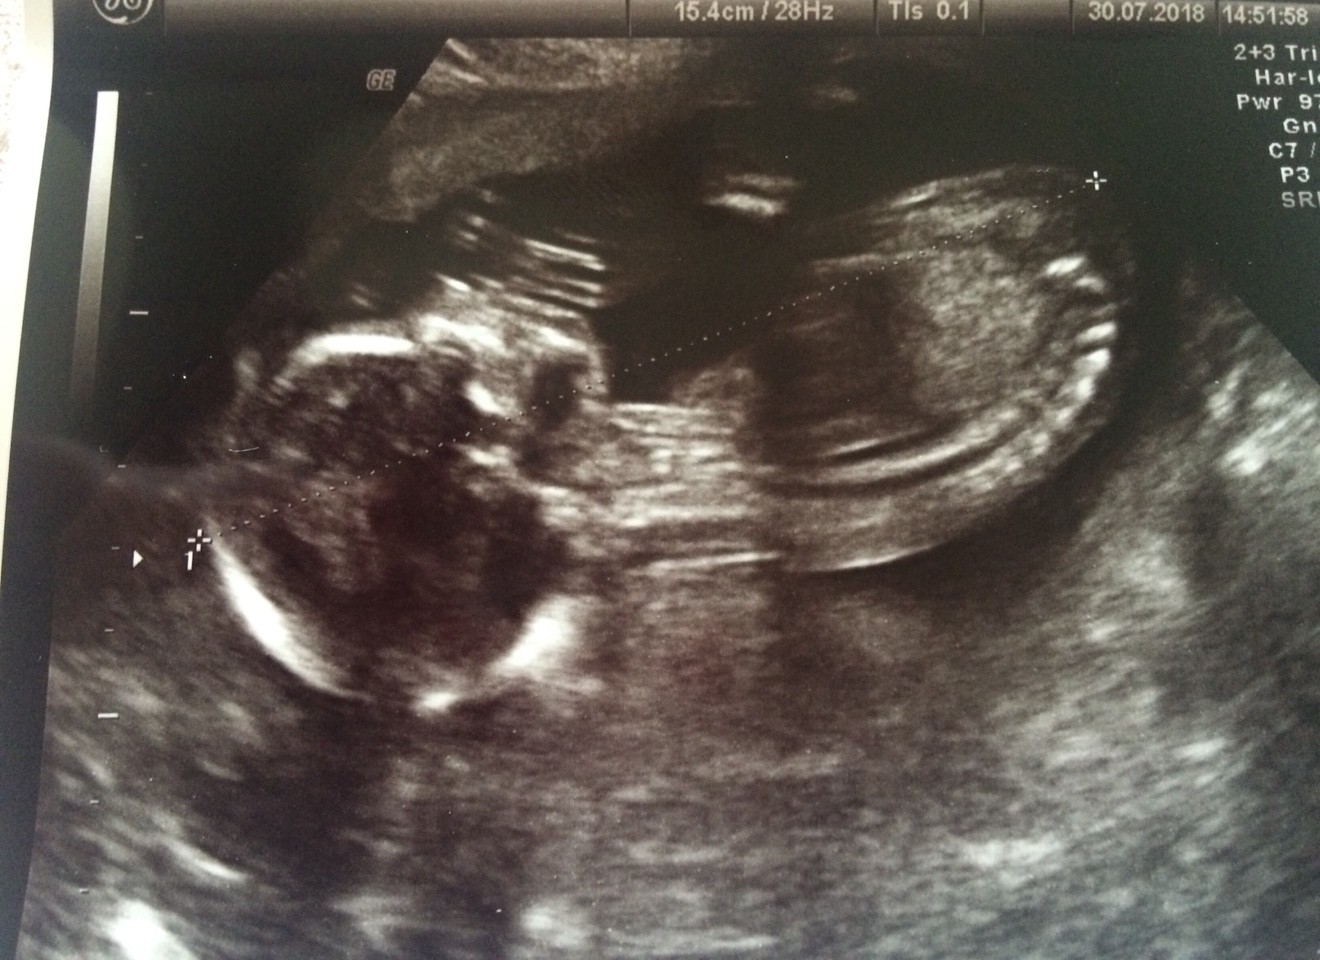

IMG_4142.JPG

IMG_4143.JPG

Niunia zdrowa i od głowy do pupy ma 12.5cm. Lekarz mój mówił, że już mierzy się z nogami, ale tak się Maluch ułożył, że było cieżko. Ale nogi są i ręce, widziałam [emoji12]